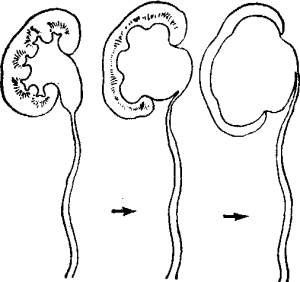

腎積水腎積水的手術治療應早期進行。合理的套用整形手術,糾正腎盂輸尿管連線部異常,爭取腎功能的較大恢復。腎積水嚴重,腎功能破壞十分嚴重對側腎正常者,可作腎切除術。

手術的原則是梗阻較輕,腎盂腎盞擴張下嚴重時,作單純矯形手術;擴張明顯者,應切除病變的狹窄段及過度擴張的腎盂,再作吻合術;更嚴重者作腎切除術。